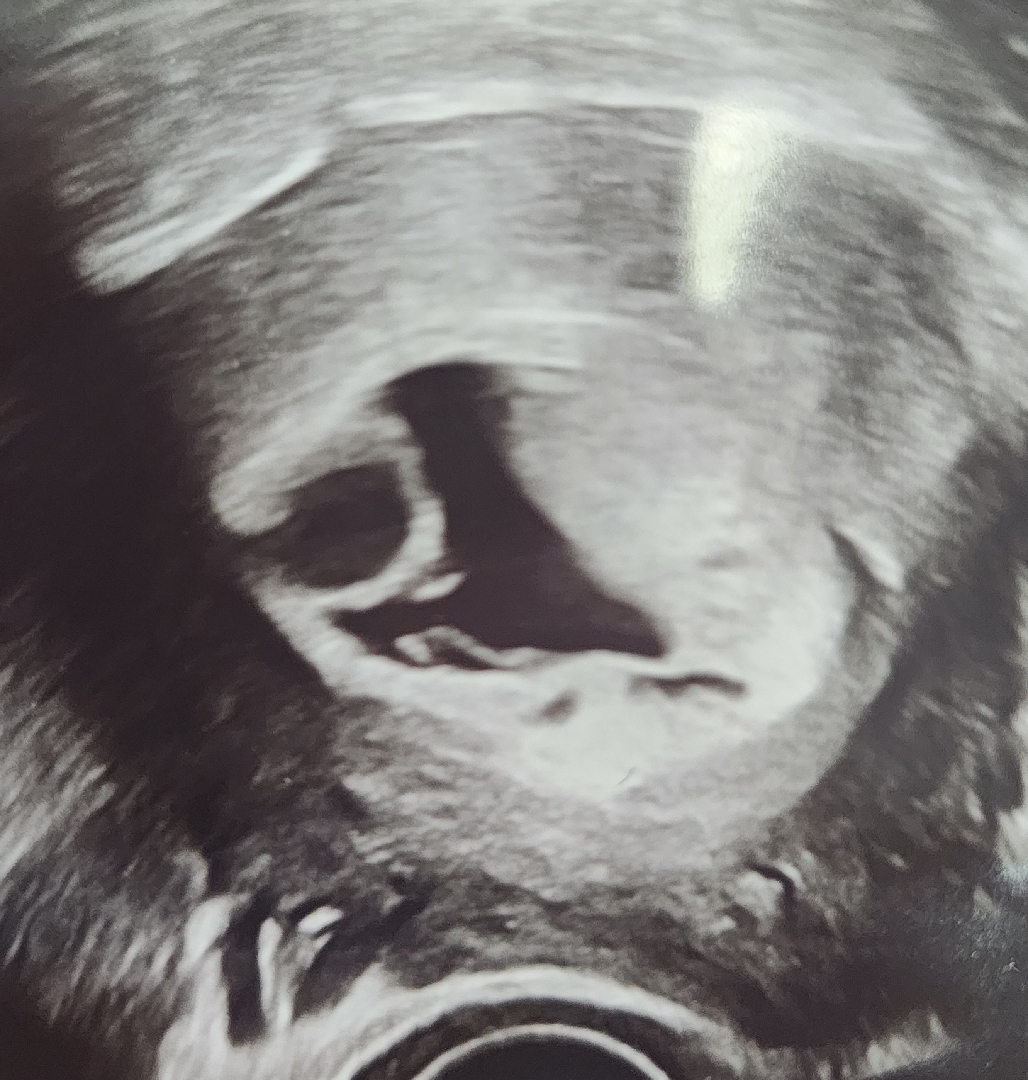

초음파상 아기집모양이 이상하고 예후가안좋데요

초음파 보여주면서 다음주에 와서도 계속이대로라면 수술해야한다고 하시는데.. 지난주엔 피고임으로 봤는데 그건아니고 혹도 있는것같고 아기집도 혹도 모두 사이즈가커졌다고 6주4일차인데 예후가 안좋다고 다음주에 와보고 안좋으면 수술해야한다고 말씀하시는데 예후좋았던분계시나요... 정말 몇년동안 기다렸던첫아이인데